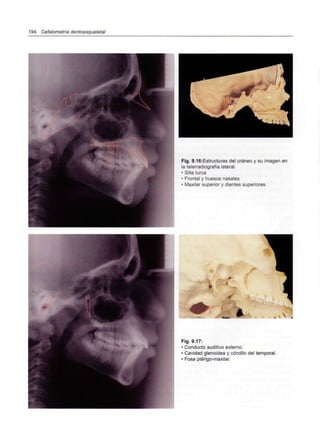

(Xi-Pm). La norma es de 47°con una desviación clí-

nica de ± 4°. Es una medida gnómica, por lo tanto

no cambia con la edad.

Variaciones en su valor deben atribuirse al tra-